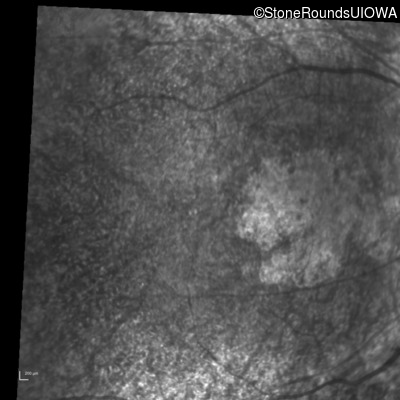

Infrared Fundus Photograph - Right - 20/1250 sc

Exemplar